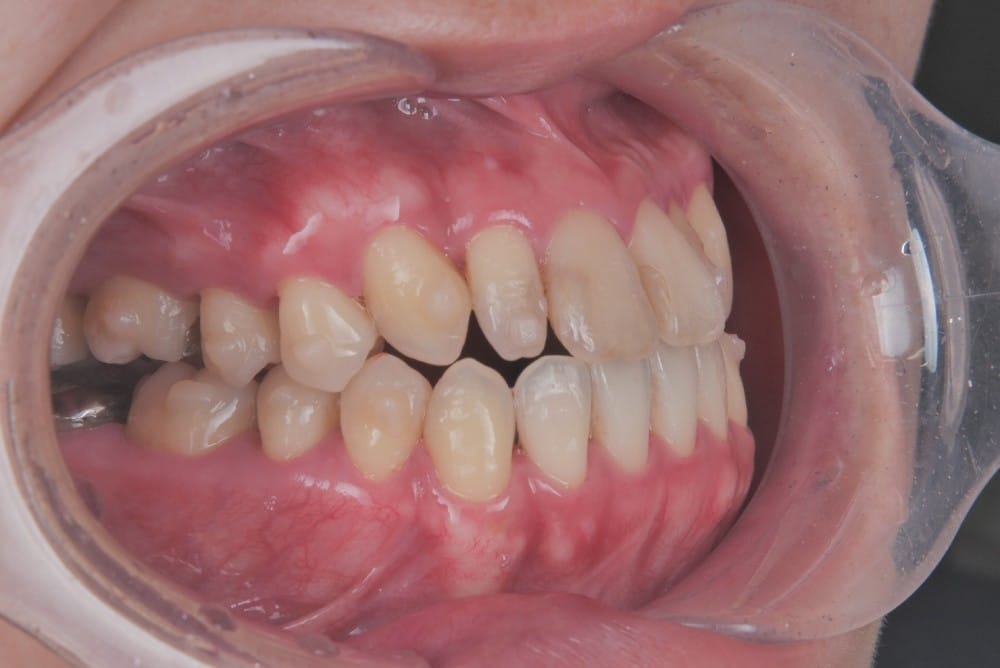

30代の女性で、受け口とガタガタを主訴にご来院されました。

治療前

分析しますと

- 骨格的な上下あごの前後差は中等度〜重度

- 噛み合わせの位置も下あごの奥歯が半分くらい前にズレていた

- 上の前歯が内側に傾斜している

というケースで、外科的な処置も検討するようなケースでした。

骨格的なズレや奥歯の噛み合わせのズレもあり、重度の受け口でしたが、上あごの前歯が内側に傾斜しているため、本来の歯の軸に戻すことで、受け口を改善できると診断し、治療を開始しました。

先ほどのケースと同じように、患者さまに外科的な手術の選択肢も提示しましたが、希望されず、横顔の変化はおそらく起こらないことを納得の上、治療をスタートいたしました。

今回のケースも奥歯の移動量が大きいため、マウスピースだけでは難しいと判断し、カリエールとよばれる装置を補助的に使用し、上下の噛み合わせの前後関係を整えることで、手術を行わずに機能面と見た目の両方が改善することにしました。

治療中の直近の写真です。生まれつき小さな歯である前から両側の2番目の歯は、被せ物をして見た目の回復をする予定にしています。

<治療前と現在の比較です>

矯正治療によって前歯の被さりを改善することで、先ほどの症例ほどではありませんが、下唇の突出感が減り、上唇も正常な位置に戻り、横顔がやわらかい印象に変化しました。